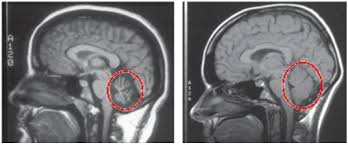

Sturge-Weberův syndrom (SWS) je vzácná vrozená porucha, která postihuje kůži, mozkové cévy a někdy i...